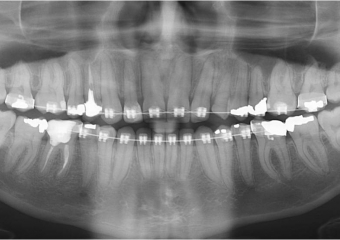

Raio X com raiz do dente 22 distalizada

Raio X após mesialização da raiz do dente 22

Raio X após a extração e implante imediato

Raio X final